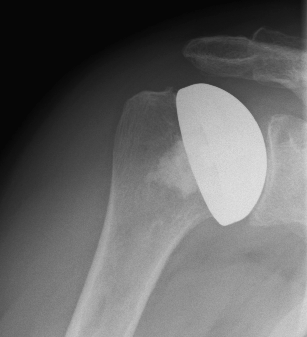

Surface replacement ("cap prosthesis" of the humeral head) in cases of mild omarthrosis and still well-preserved glenoid cavity

links: X-ray image of a cap prosthesis ("surface replacement")